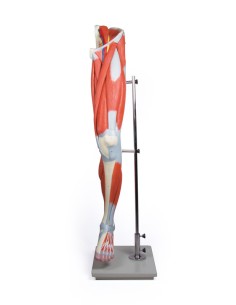

Du crâne en 22 parties à verrouillage magnétique aux modèles de colonne vertébrale, des modèles d'articulation aux modèles de cœur, chaque pièce de notre collection est conçue pour une immersion totale dans l'étude de l'anatomie humaine. Nos modèles, réalisés à partir de scans d'os réels, garantissent une expérience tactile authentique et une fidélité de poids presque identique aux originaux.

Indispensables aux étudiants comme aux professionnels, nos modèles anatomiques sont des outils pédagogiques qui permettent d'observer les structures anatomiques avec précision, en évitant les dissections ou les études invasives. Ils sont également utiles pour expliquer les pathologies aux patients, ce qui rend la communication plus efficace et permet de gagner un temps précieux.